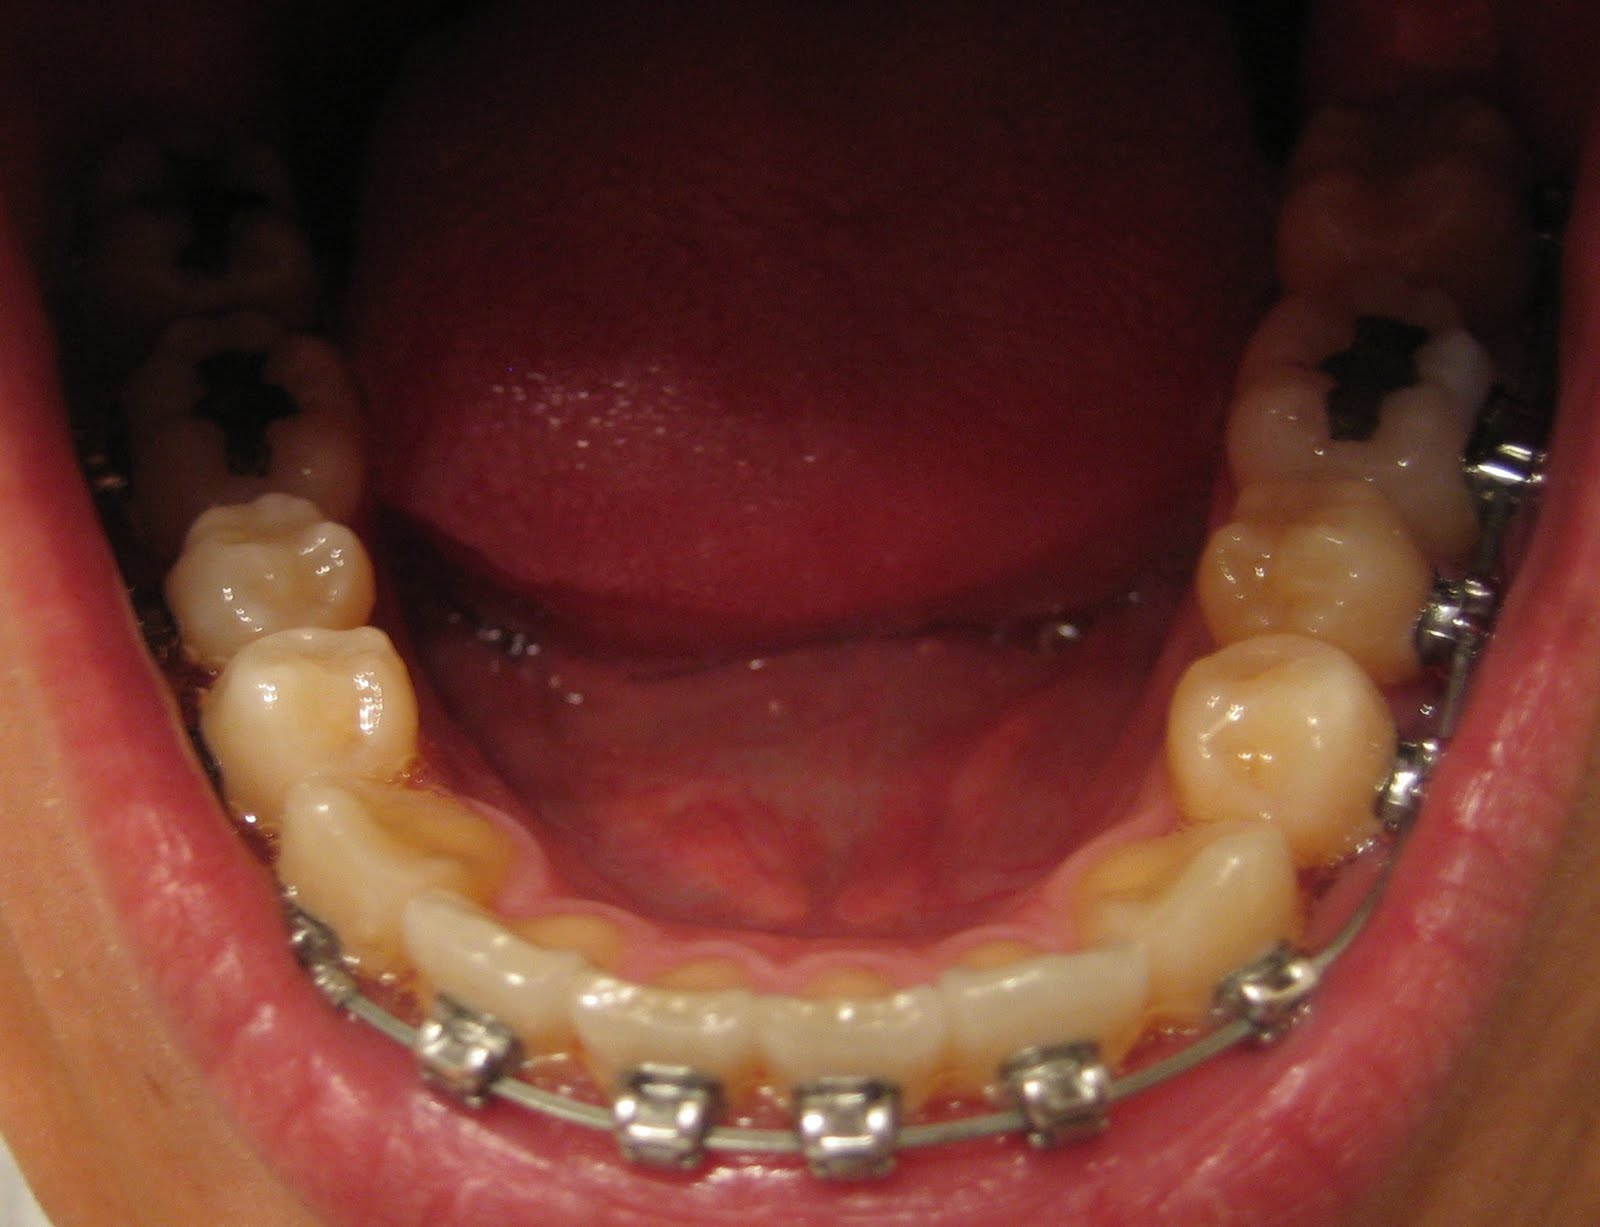

My Damon Clear Braces Week 37

My Damon Clear Braces Week 15 Third wire change and power chains! Damon Braces With Power Chain Damon braces typically cost between $3,800 and $8,000, with the price depending on the severity of your malocclusion and the extent of correction required. While they are more expensive than traditional metal braces, private insurance may help cover the treatment costs. A power chain is a rubber band that’s stretched across multiple teeth to apply additional forces to move your. Damon Braces With Power Chain.

My Damon Clear Braces Week 37 Damon Braces With Power Chain But suddenly, you’re hearing a brand new term—“power chains.” what exactly are these power chains, and why does. Do damon braces need power chains? Unlike conventional braces, the damon system uses gentle forces designed to protect the health of your teeth and gums while in treatment. Orthodontists or dentists use power chains to hold and connect the brackets, but sometimes. Damon Braces With Power Chain.

My Damon Clear Braces Week 17 (Progress picture) Damon Braces With Power Chain But suddenly, you’re hearing a brand new term—“power chains.” what exactly are these power chains, and why does. Do damon braces need power chains? They’re most commonly used to help close spaces, rotate teeth, or make space for a tooth that doesn’t have enough room to straighten out. Orthodontists or dentists use power chains to hold and connect the brackets,. Damon Braces With Power Chain.